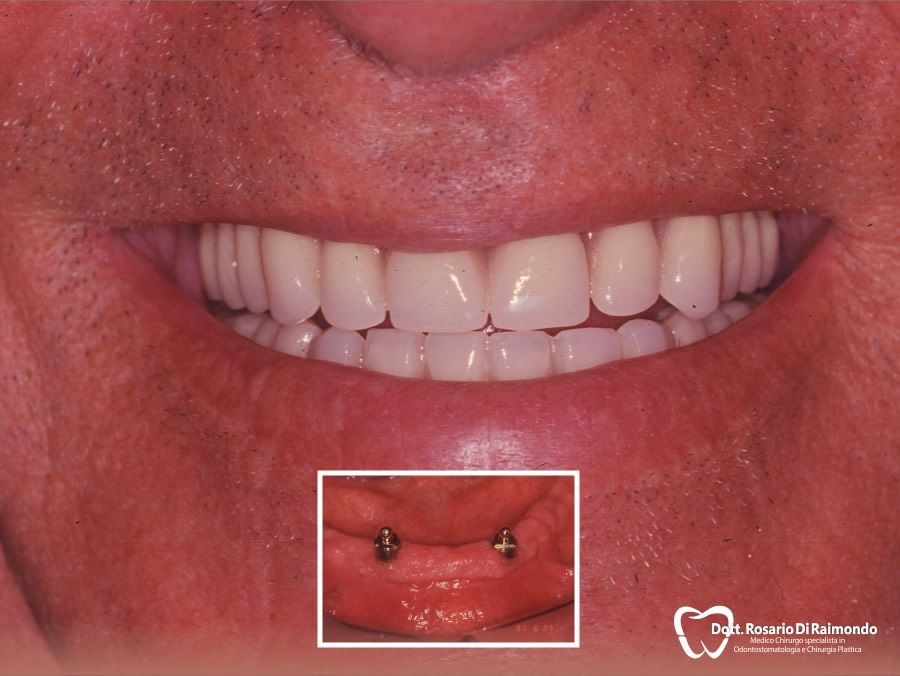

Casi Trattati

Di seguito riportiamo alcune fotografie di casi di Implantologia già trattati.